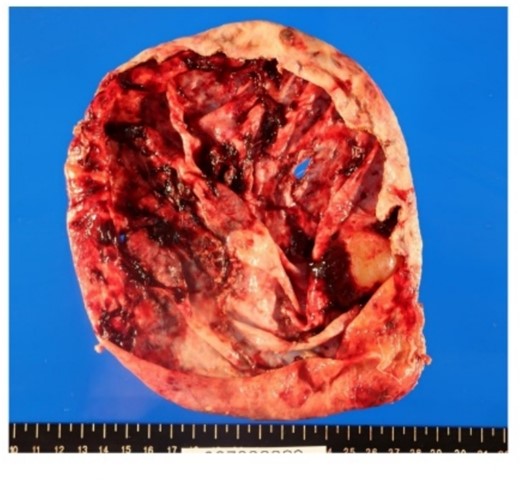

Surgical specimen showed no neoplastic lesion (Fig. 5). Pathological diagnosis was a non-parasitic simple hepatic cyst with acute inflammation and hemorrhage. The cystic wall presented bile duct epithelium and liver lobules. Immunohistochemical staining showed that only CA19-9 was positive in the hepatic cyst wall epithelium (Fig. 6). The patient’s serum levels of CA19-9, CA125 and CEA were 164.0 U/mL, 126.3 U/mL, and 1.0 ng/mL, respectively, on postoperative day 23. A follow-up abdominal CT scan performed 2 months after the surgery did not show any sign of tumor.

In hematoxylin eosin staining (a), pathological findings of the cystic wall presented bile duct epithelium and liver lobules. Immunohistochemical, the hepatic cyst wall epithelium was only CA19-9 (b) positive, negative for CEA (c) nor CA125 (d).